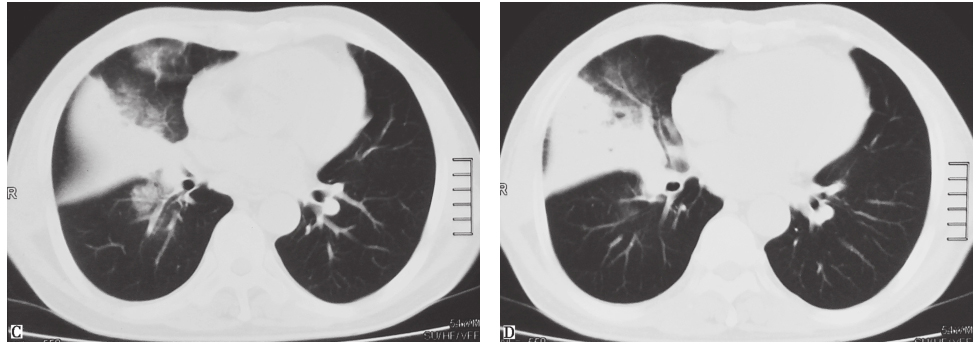

可为吸入性肺脓肿、血源性肺脓肿及继发性肺脓肿。吸入性肺脓肿多为单发,伴有咳脓臭痰、高热。血源性肺脓肿多由细菌血行播散所致,常见于金黄色葡萄球菌败血症,可表现为多发小的薄壁空洞,即液气囊腔(图3),可进展迅速,常伴有发热。继发性肺脓肿可为肺炎后肺脓肿、阿米巴性肺脓肿等,多为单发空洞。

肺结核空洞常为厚壁空洞,周围可有肉芽肿性肺实变、纤维化或钙化区,可伴有卫星灶或树芽征(图4)。患者可有乏力、低热、盗汗等结核中毒症状,或临床症状不典型。

图3 金黄色葡萄球菌败血症所致肺脓肿胸部CT表现

图4 肺结核空洞胸部CT表现

胸部CT见周围卫星灶及树芽征